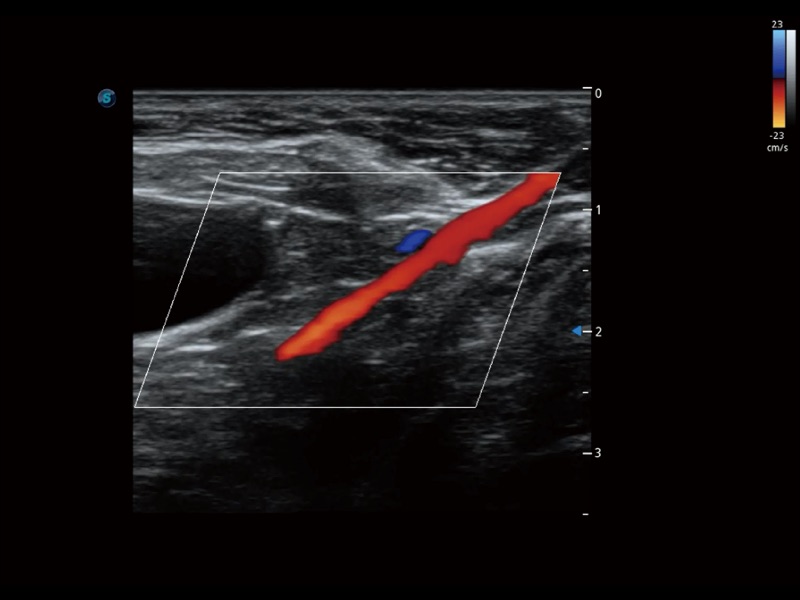

(犬)肾脏显微血流

(犬)髂动脉血流